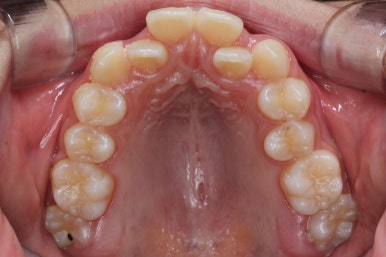

윗니들만 보게 되면 더 드라마틱한 것을 볼 수 있습니다.

악궁확장장치는 유지기간 이 후 다 제거가 되었고, 치아들이 매우 가지런해지는 것을 볼 수 있습니다.

이제 조금만 더 정리가 되면 장치 제거가 가능하겠네요.